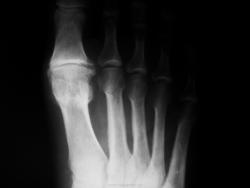

Один из методов лечения поперечного палоскостопия с выраженым дефартрозом 1 пл-ф суст. Операция Вредена-Мейо+ операция Брандеса+формирование поперечной связки стопы+протезирование. Померяйте какой сейчас Hallux valgus, опишите состояние культи и протеза.